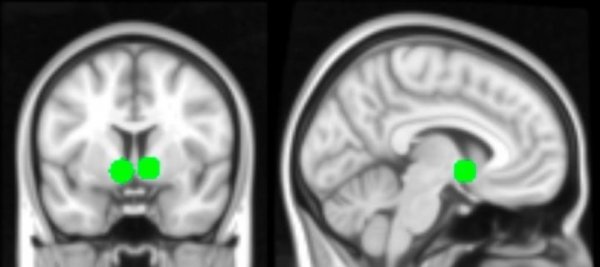

该研究的作者Lauren Sherman,是一位来自脑成像中心以及UCLA儿童数字媒体中心的研究者。她表示,当青少年看到自己的照片获得了许多“赞”时,大脑的许多脑区都被激活,其中激活程度最高的是纹状体的一部分,叫做伏隔核,是大脑奖赏回路的一部分,这一奖赏回路在青少年时期尤为敏感。当青少年看到自己的照片得到了许多“赞”时,研究者还观察到了社会大脑区域以及视觉注意相关脑区的激活。

当青少年在观看危险图片时,大脑中认知控制与反应抑制相关区域的激活水平低于观看中性图片时,这些区域包括大脑的背侧前扣带皮层、双边前额叶皮质和侧顶叶皮质。

Dapretto表示,这些脑区与决策相关,能够阻止或批准我们进行某项活动。看到危险图片时激活水平下降,或许降低了青少年的防范程度。